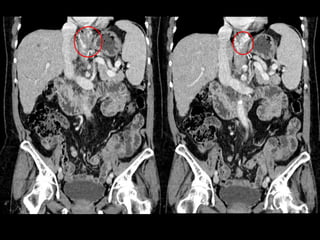

 Hallazgos Radiológicos:

 Irregularidad de contornos hepáticos

 Hipertensión portal

 Varices esofágicas

 Esplenomegalia

Daño hepático crónico

Terminado el examen… Protocolo Aplicado  DHC  Hepatocarcinoma  Rendimiento del método:  Caracterización de lesiones  Control de quistes  Control preoperatorio  Respecto a la Patología:  Protocolo adecuado  Hallazgos Radiológicos:  Irregularidad de contornos hepáticos  Hipertensión portal  Varices esofágicas  Esplenomegalia